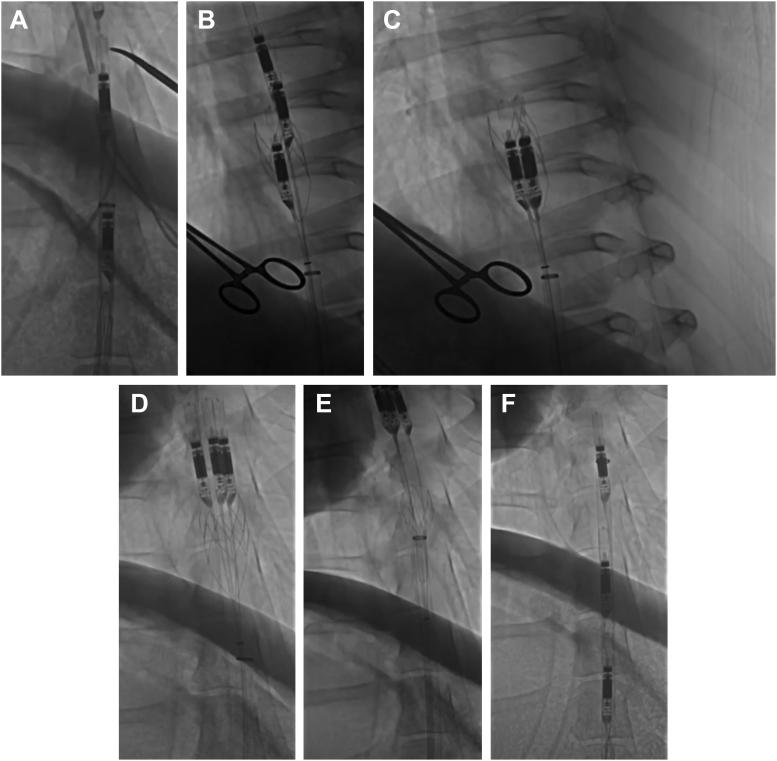

ModulHeart (Puzzle Medical Devices Inc) is a modular device providing hemodynamic support through 3 endovascular pumps inserted in series and assembled in parallel into a self-expandable anchor implanted in the descending aorta. The current study evaluates the feasibility and safety of cardiorenal support with ModulHeart among patients undergoing high-risk percutaneous coronary intervention (PCI).

On June 28 and 29, 2022, 4 patients were enrolled and underwent high-risk PCI with ModulHeart implanted via transfemoral approach. All 4 patients achieved procedural success. The mean delivery time was 8 minutes, the mean support time was 49 minutes, and the mean pump removal time was 7 minutes. The mean pressure gradient across the pump was 5 ± 2 mm Hg. Under ModulHeart support, cardiac index increased by 25%, central venous pressure decreased by 37%, and left ventricular end-diastolic pressure decreased by 78%. Urine output increased by ∼9-fold after 15 minutes of support. No device malfunction or procedural or device-related adverse events occurred. There was no evidence of pump thrombosis. All 4 patients were alive at 30 days.